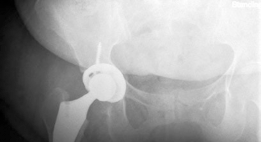

Reduction and Closure

The hip is reduced by applying axial traction and internally rotating the limb. Fluoroscopy is used to assess leg length (comparing the teardrop-to-lesser trochanter distance bilaterally) and offset. Clinical stability is tested by taking the hip through a full range of motion, specifically checking for anterior impingement in extension and external rotation.

Clinical & Radiographic Imaging